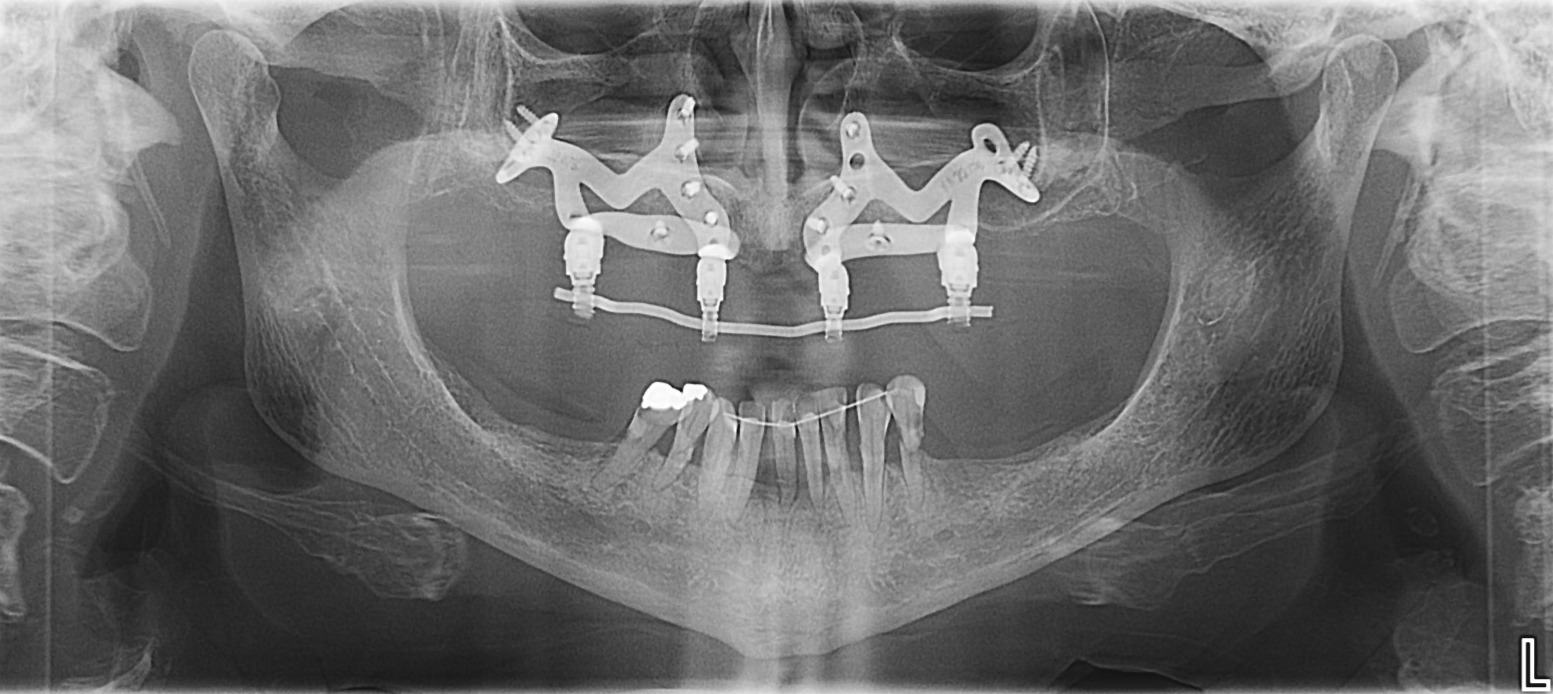

Subperiostalni zobni implantati so najnovejši način All-on-4 ali All-on-6 sistema zobnih vsadkov, ki se uporabljajo namesto invazivnih Zygoma zobnih implantatov za paciente z premalo ali ekstremnim pomanjkanjem zobne kosti. Smo visoko usposobljeni strokovnjaki in zagotavljamo vse pogoje, ki so potrebni za izpolnjevanje najvišjih standardov zobozdravstvenih in implantoloških storitev ter kakovosti za opravljanje tovrstnih zobozdravstvenih in zobno kirurških posegov.

Prednosti posamičnih subperiostalnih zobnih vsadkov po medtodi All-on-4 in All-on-6: